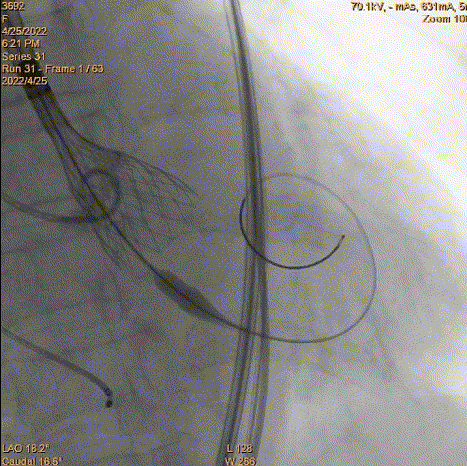

6、瓣膜回收和再释放:到达2/3后小弯侧较深,经多角度评估评估较深,起搏回收再次释放。

瓣膜再次释放

7、释放完成:第二次释放评估深度合适,缓慢释放脱钩,同轴性良好。撤递送系统,撤抓捕器。

二次评估深度

缓慢脱钩